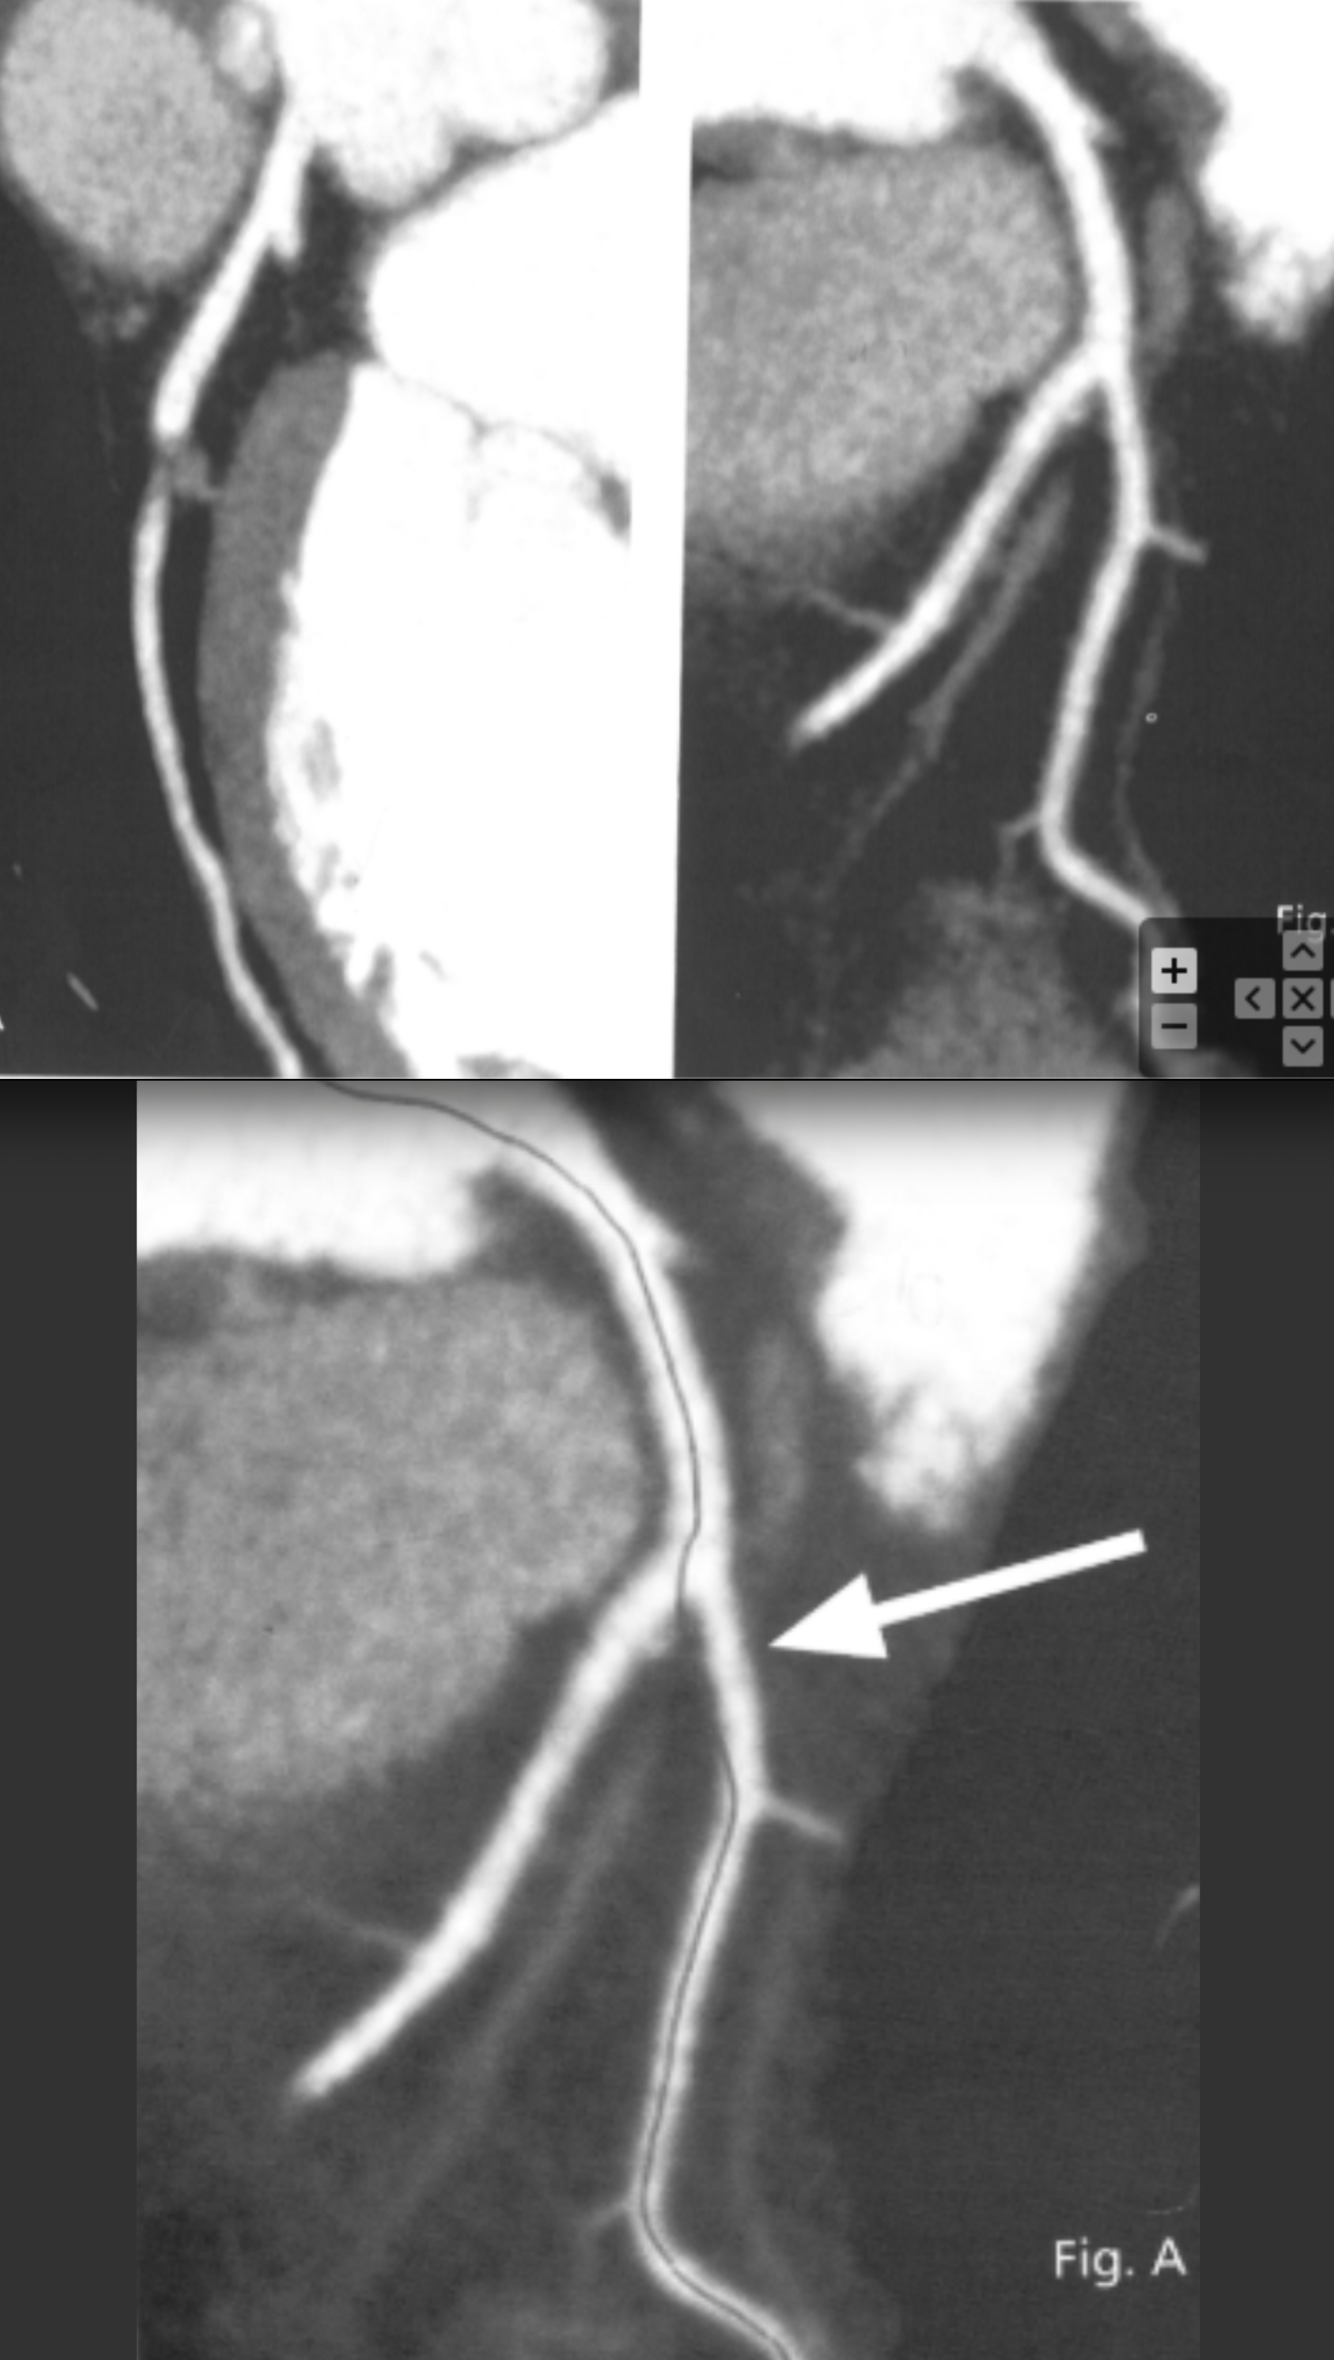

Describe the findings and most likely explanation for the discrepancy

The vessel line is incorrect

Describe the most likely finding:

Subtotal occlusion